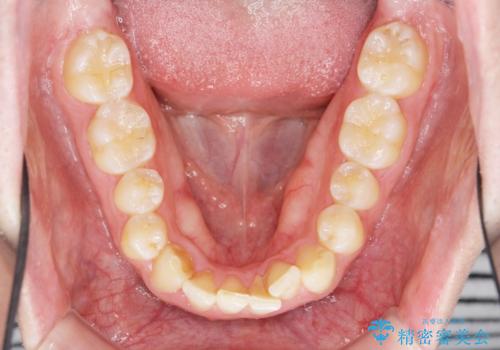

前歯が隠れていて見えない クロスバイトの矯正治療

- 「前歯が1本隠れていて見えない、歯並びを矯正治療で改善したい。」と希望され来院されました。

奥に隠れている前歯を並べられるスペースを確保したのち、歯並びを整えていきます。

前歯のスペース不足により1本だけ後方に位置している状態でしたが、しっかりとスペースを確保し配列することができました。